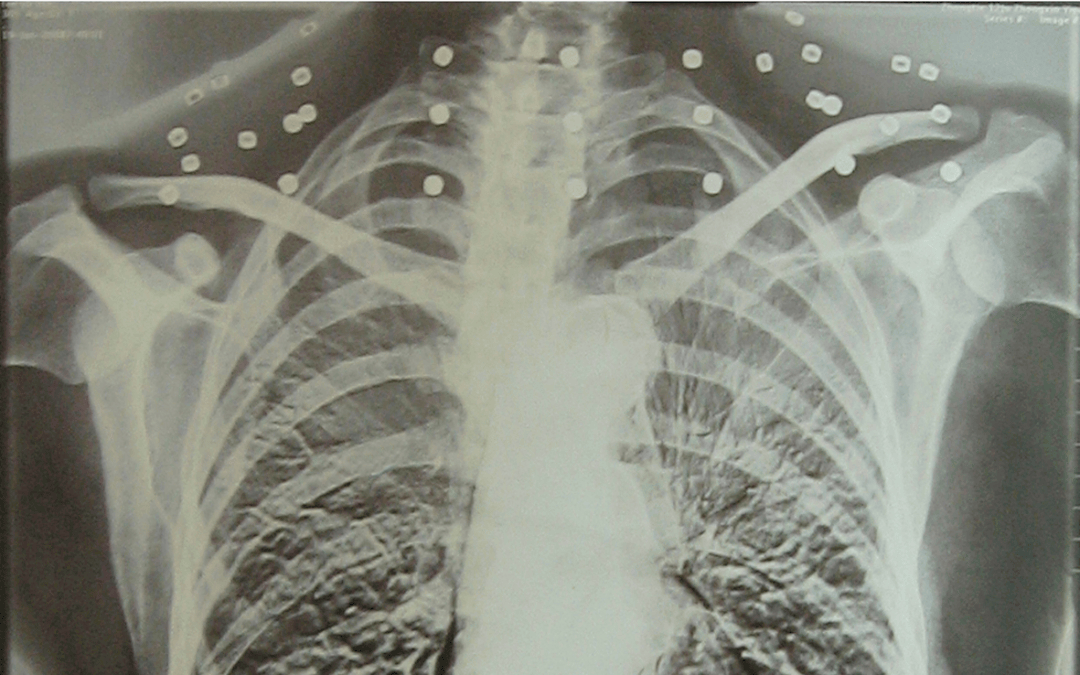

这张照片

是今年82岁的吴以先老人

拍摄的一张CT照

但实际上是

吴以先的颈部和腹部

共分布着33枚弹片

但是打进身体里的弹片

一直留在了体内

他体内的弹片都没有取出

每到天气变化时

身体留有弹片的位置就有痛感

但吴以先不考虑取出弹片

在他看来

这是他与战友并肩作战的见证

是他的勋章

与吴以先身上那33枚弹片

一起永远烙印在他心中

33枚“军功章”

是一名军人的光荣